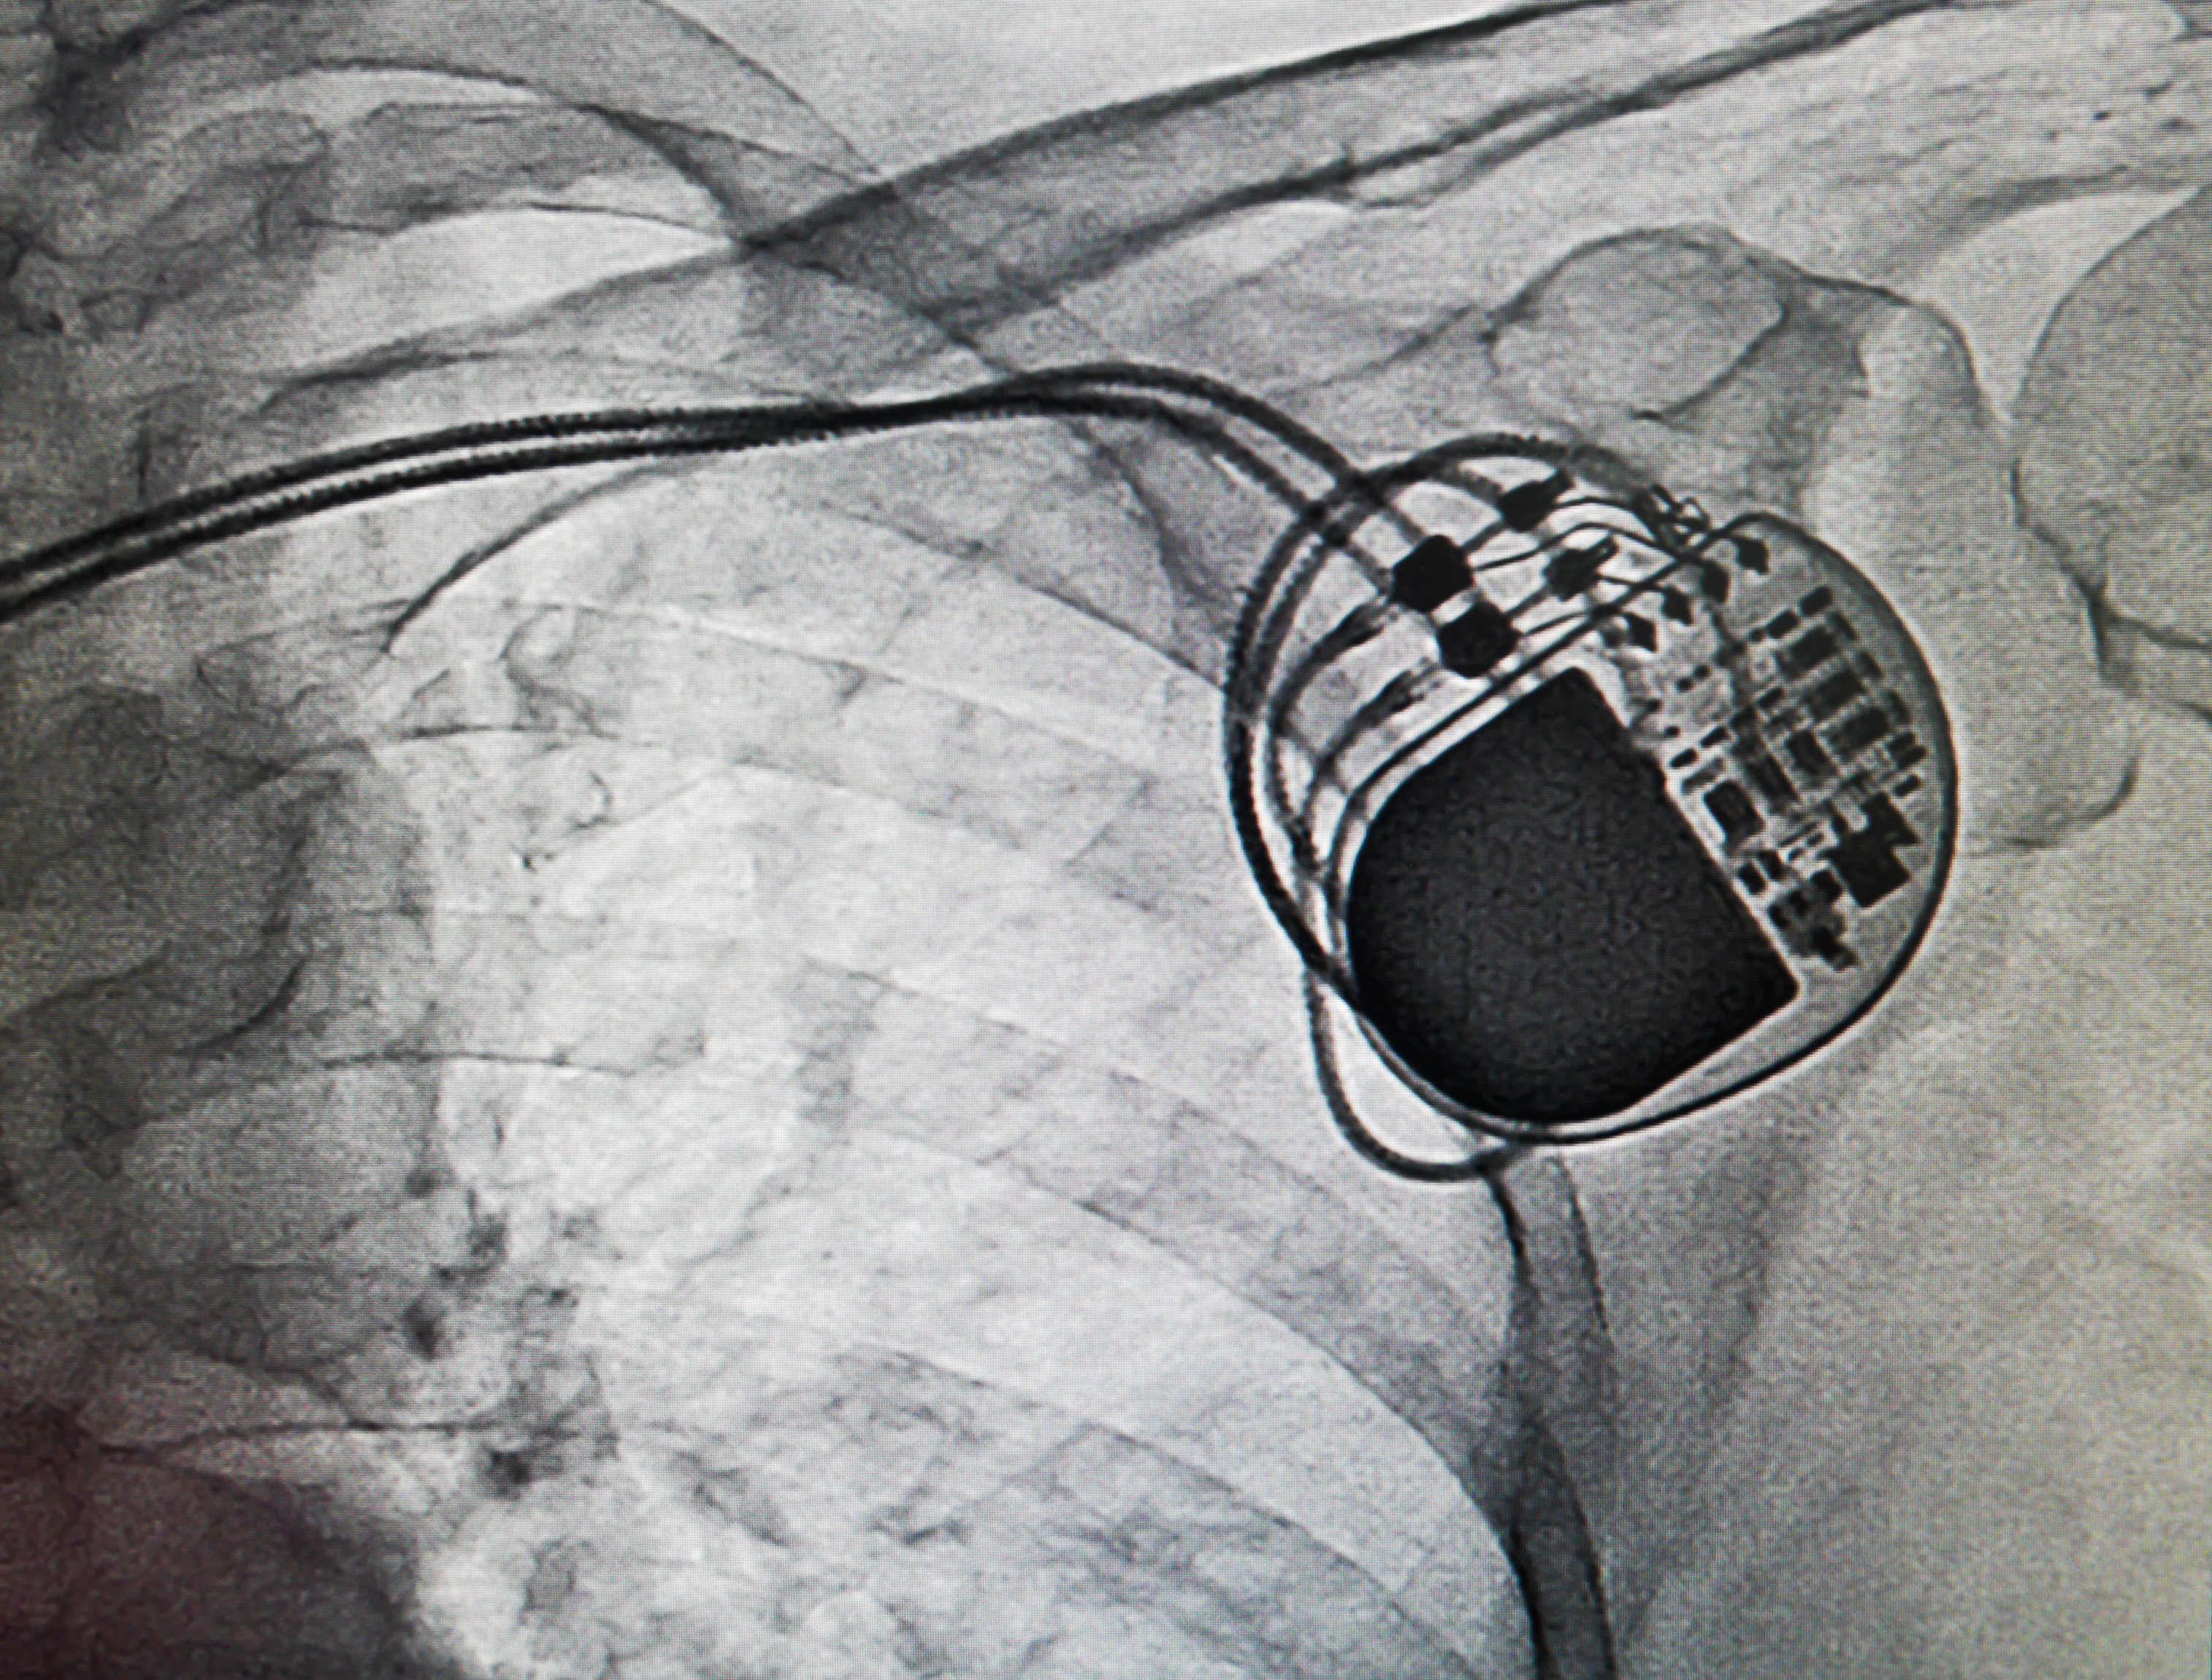

Alarmingly Low Rates of Extraction for CIED Infection Despite National and International Recommendations: a Nationwide Observational Study among Over 10,000 Medicare Patients

Key Points Prompt and complete removal of CIED systems is strongly recommended…